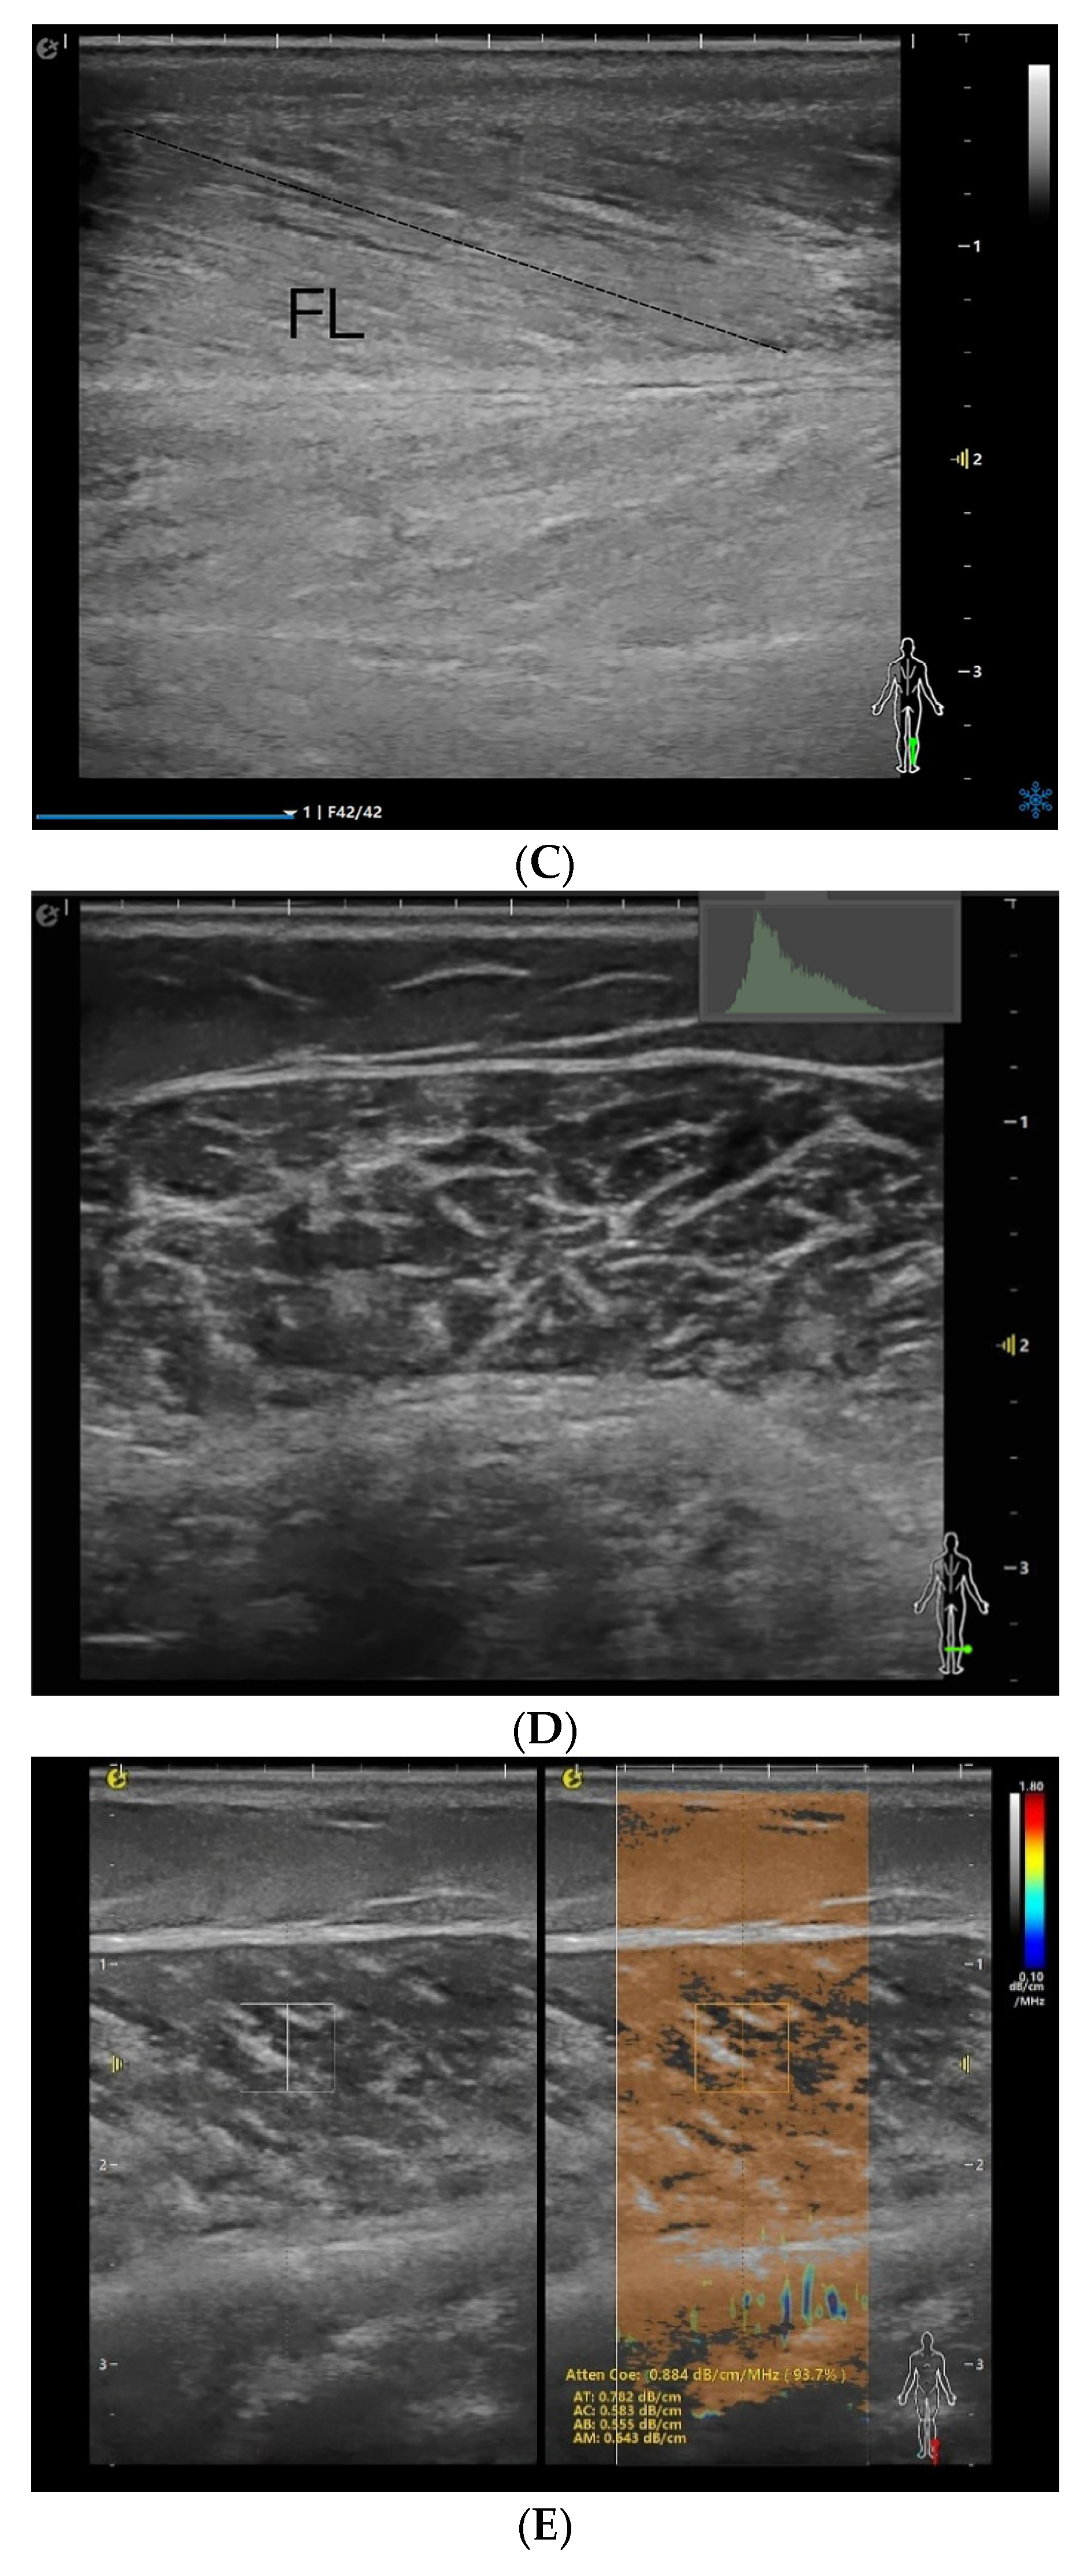

2.4. Ultrasound Examination

3.2. Ultrasound Parameter